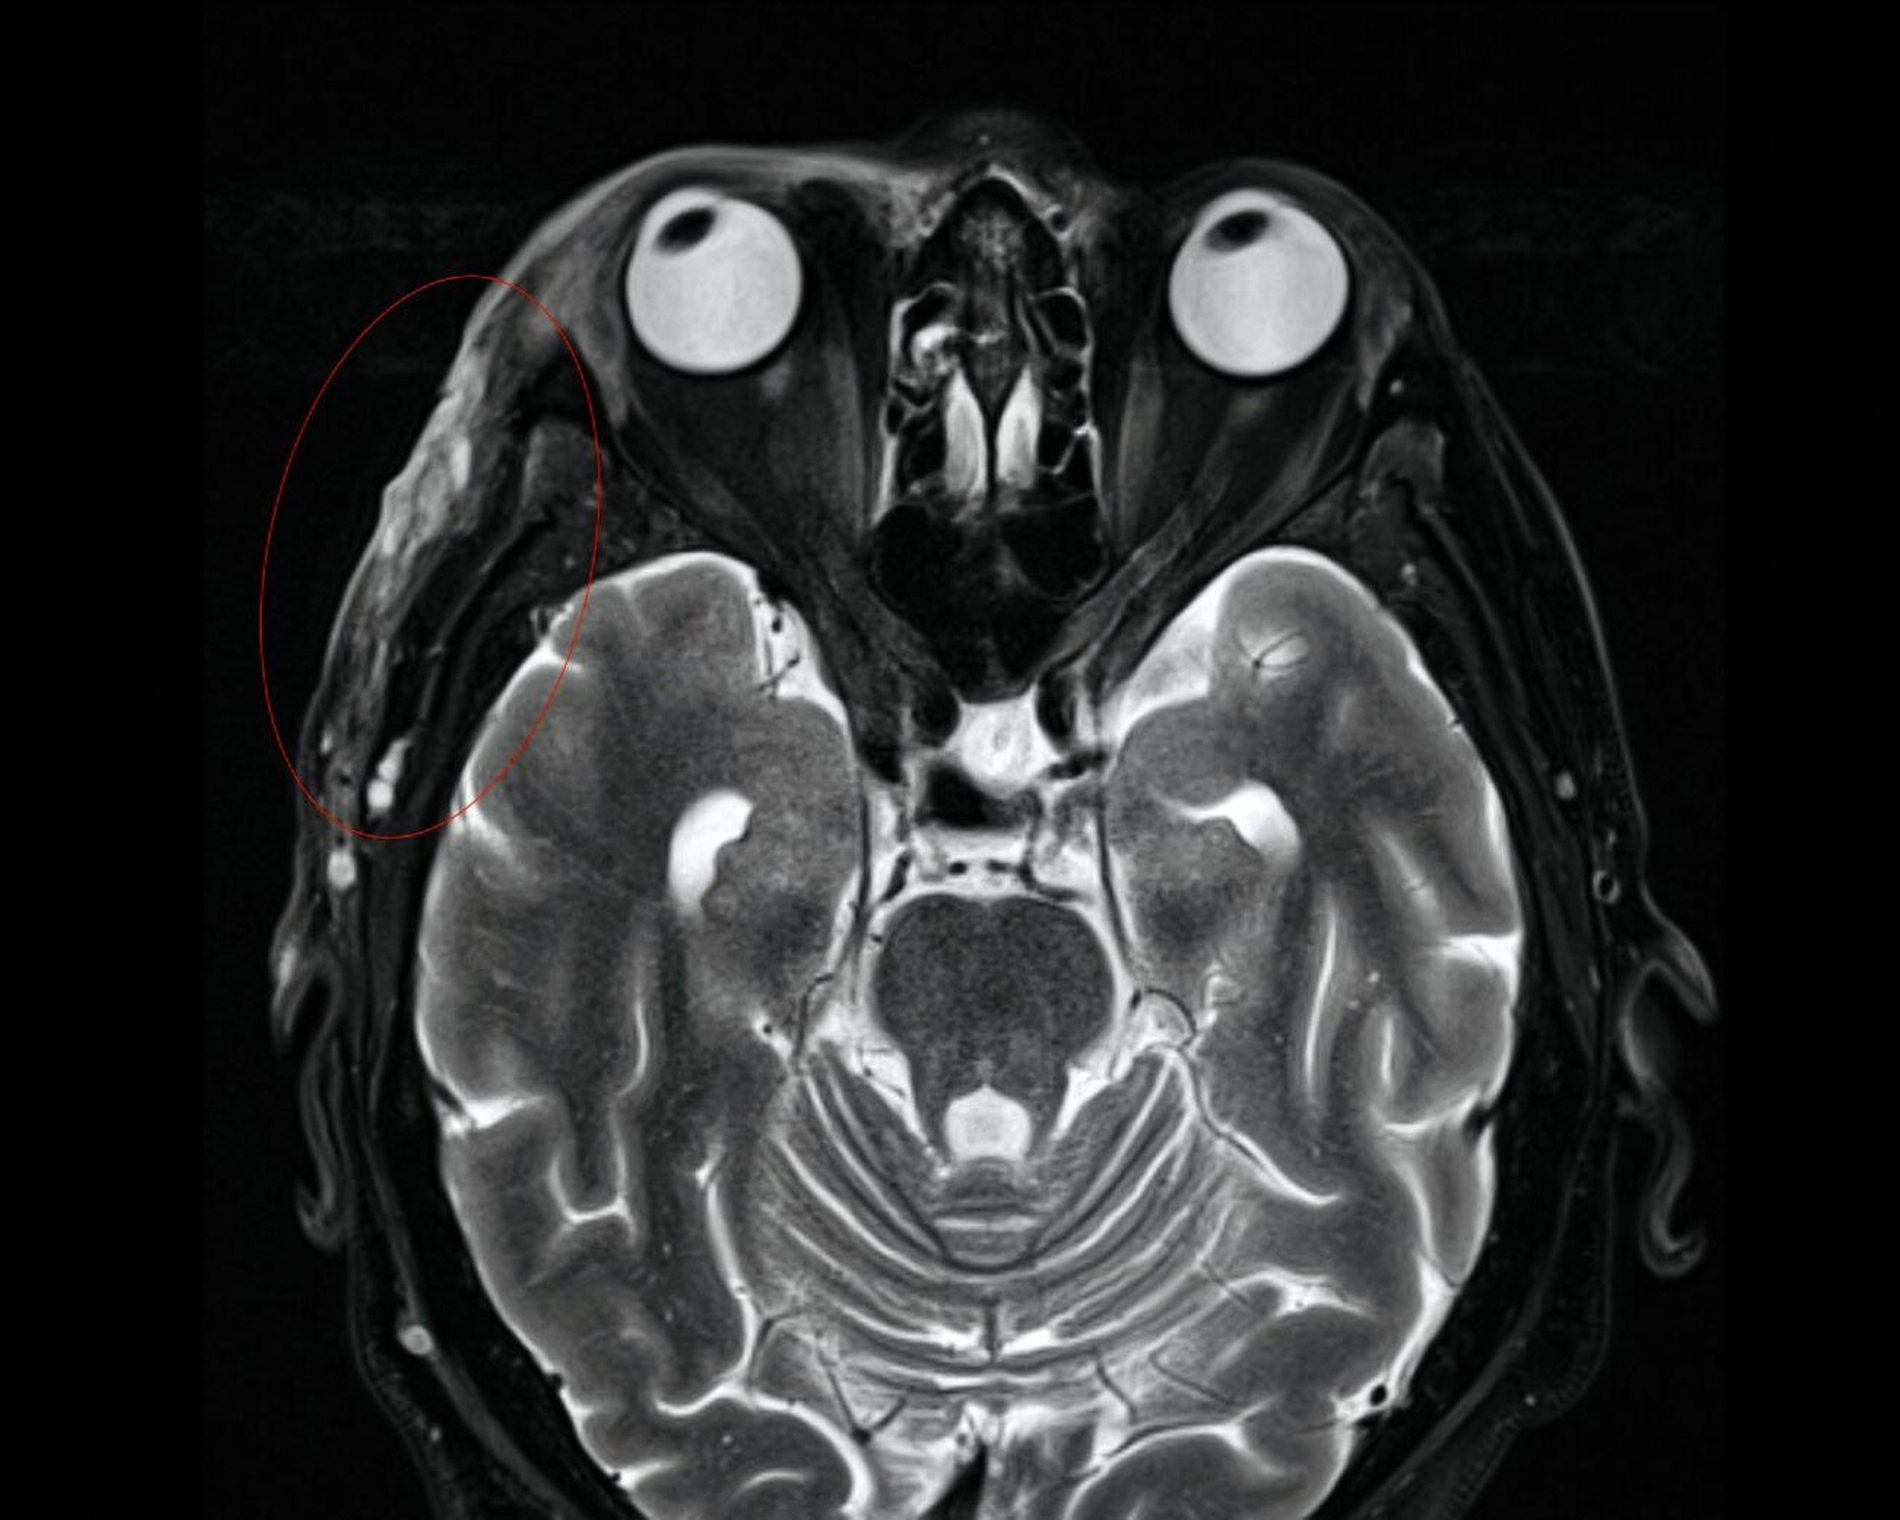

Aufgrund des klinisch-makroskopischen Bildes mit progressiver Gewebenekrose, fehlender segmentaler wasserklarer Bläschen wurde der Zoster durch PCR ausgeschlossen und die antivirale Therapie beendet. Ein maligner Tumor fand sich in der Probeexzision vom Aufnahmetag nicht. Ebenso wurde per Computertomografie (CT) und Magnetresonanztomografie (MRT) eine intrazerebrale und intraorbitale Beteiligung ausgeschlossen. Allerdings zeigten sich rechts temporoparietal eine zunehmende Dichteanhebung, paraseptale Lufteinschlüsse und eine Schwellung des Weichgewebes mit progredienter Ausweitung im Vergleich zu den Aufnahmen einen Monat zuvor (Abbildungen 2 und 3). In der Zusammenschau von Klinik, Bildgebung und dem positiven Befund eines Staphylococcus aureus in der zwischenzeitlich erfolgten mikrobiologischen Analyse wurde die Diagnose einer akut nekrotisierenden Fasziitis gestellt.

Im fortgeschrittenen Stadium lässt sich eine Krepitation der Weichteile vernehmen, die radiologisch als eingeschlossene Luftblasen verifizierbar ist. CT und MRT sind somit wichtige Hilfsmittel, um Differenzialdiagnosen auszuschließen und die Ausbreitung in den Weichteilen und auf Faszienebene abzuschätzen, lange bevor kutane Nekrosen sichtbar sind [Wysoki et al., 1997].

Die Maden-Therapie stellt in unseren Augen jedoch einen besonderen Therapieansatz und nicht das Regelvorgehen dar. Sie sollte in unseren Augen bei der nekrotisierenden Fasziitis immer nur dann zur Anwendung kommen, wenn es die Ausdehnung des Befunds noch zulässt. In unserem Fall lag zwar ein ausgedehntes und mit kritischen anatomischen Strukturen beteiligtes Wundareal vor, die Infektion lag jedoch lediglich im Bereich der superfizialen, gut durchbluteten Gesichtsweichteile und war daher der Maden-Therapie zugänglich. Eine Beteiligung tieferer Strukturen (Orbita, Muskelnekrosen) war CT-morphologisch vorab ausgeschlossen worden.